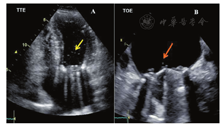

多数情况下,TTE检查人工二尖瓣/三尖瓣的左右心房侧(LA/RA)将受到声影遮挡,降低了人工二尖瓣或三尖瓣反流(MR、TR)、血栓或赘生物的检出敏感性(图5A,图5B)。而TOE检查可更清晰地显示人工二尖瓣/三尖瓣的LA/RA侧(图5C,图5D)。在主动脉瓣位置,TTE显示瓣膜的后方存在声影(图4A),而TOE显示瓣膜的前方存在声影(图4C,图4D,图4E)[88,89]。对于支架型瓣膜,应仔细调整超声声束与血流平行以避免支架和缝合环引起的伪像[90]。